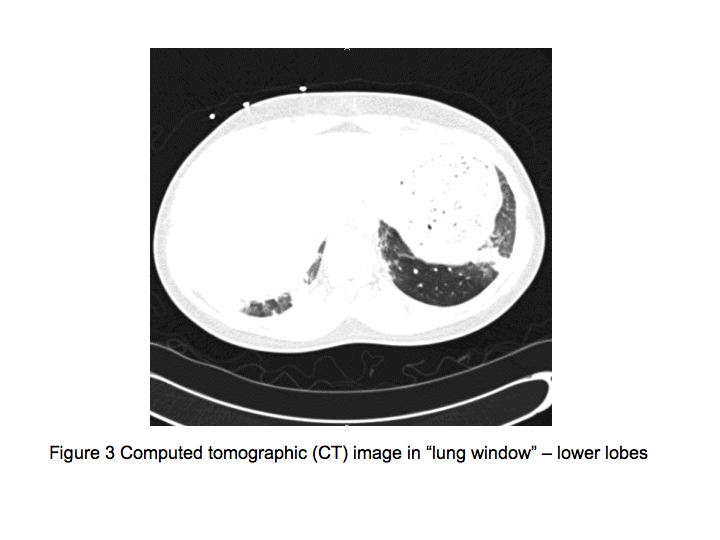

The patient was admitted to the medical floor and was started empirically on antibiotics. Cultures were obtained and an HIV test was done. Bronchoscopy was planned the next day which revealed diffuse erythema and hemorrhage in both the bronchial trees as shown in Fig. 5.